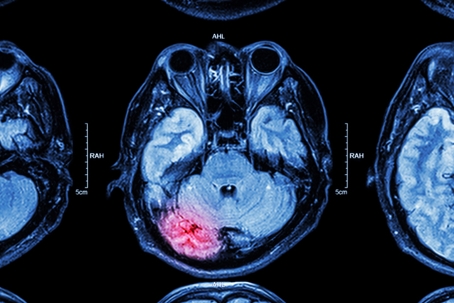

MRI Brain Scan

A concussion is a mild traumatic brain injury (TBI) that disrupts normal brain function. This temporary impairment is often caused by a bump, blow, or jolt to the head. However, a concussion can also occur from a forceful hit to the body that causes the head to move rapidly back and forth.